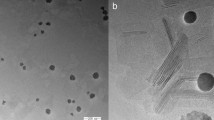

Emulsion and microparticle fabrication. Drug dimers were dissolved in dichloromethane at 25% w/v, and 200 µl of this solution was then added to 400 ml of an aqueous solution of 1% sodium dodecyl sulfate (SDS, Sigma-Aldrich) through a Shirasu Porous Glass membrane (SPG Technology Co., Ltd). Samples were stirred for 1 h at room temperature. Serial centrifugation was used to remove residual SDS and collect microparticles. Microparticles were re-suspended in 0.5% carboxymethylcellulose (CMC, Sigma) in Milli-Q water at a concentration of 1 g/ml. 50 μl of the microparticle suspension was deposited onto carbon tape and left to dry overnight. Once dry, the samples were sputter-coated with gold at a thickness of 15 nm. Images were obtained at ×300 magnification. Microparticle diameter measurements were obtained using ImageJ (v. 1.8.0), in which the diameters of the microparticles were determined by normalizing the scale bar on the images with the corresponding distance in pixels. All microspheres that were un-obstructed and completely visible in the images were measured. Four batches of microparticles were assessed, with a minimum 200 microparticles measured per batch.

To prepare nanoparticles, dimers were dissolved in DCM at 25% w/v, and 200 µl of the solution was added to 3.8 ml of 1% SDS and sonicated for 1 min. Samples were then washed and nanoparticles collected by serial centrifugation. Nanoparticle size distributions were assessed using a DelsaMax Pro (Beckman Coulter).

TEM

A 5 µl droplet of nanoparticles at ~0.2 mg/ml was placed on a continuous carbon-coated copper grid (200 mesh). Excess water was removed by blotting with filter paper from the bottom of the grid, and left to dry overnight at room temperature. Samples were imaged with a Philips CM10 TEM.